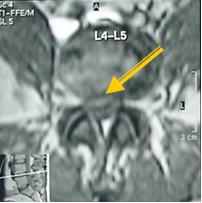

2 стадия — экструзия — выбухание в позвоночный канал элементов фиброзного кольца и дегенерированного пульпозного ядра;

— пролaпс — выпадение в позвоночный канал через дефекты фиброзного кольца фрагментов дегенерированного пульпозного ядра, сохраняющих связь с диском;

Экструзия (трансанулярная) с разрывом продольной связки: